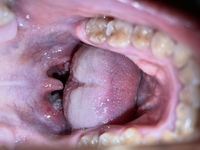

ノドに白いもの カテゴリ 診療について 18年9月28日 岩倉市の「いのうえ耳鼻咽喉科」です。 先日のことです。 「 ノドに白いものがある 」とのことで患者さんが来られました。 ノドを診てみると↓ 粘膜に発生する炎症で、扁桃腺の周辺にもできます。 丸くて白っぽい 形状の場合が多く、患部に触れると 激痛が走るケースも あります。喉の奥にある白い玉の正体は 「膿栓(のうせん)」 といい、臭い玉は俗称です。 大きさは 直径1mm〜1cmくらい にまでなるものもあるとされており、 潰すとドブのような強烈な悪臭 があります。 色は 白やクリーム色 で、 ほぼ球体形 です。